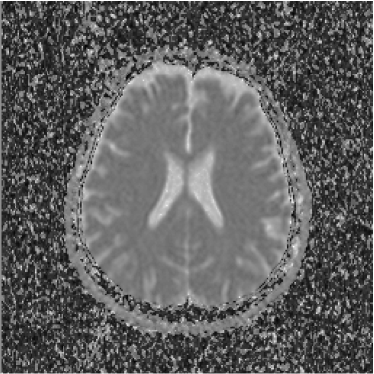

Refer to caption

Figure 1: Axial DW-MR image of 13th slice with diffusion exponent of 0 s/mm2

To perform the training we chose 13th slice of each volume sample (figures 1, 2 and 3), once this slice shows the temporal corni of the lateral ventriculi. The exhibition of such structures facilitates the analysis of the specialist and helps him to find a correlation between data generated by our computational tool and a priori specialist knowledge. Furthermore, slice 13 presents a considerable amount of artifacts out of the cranial region.